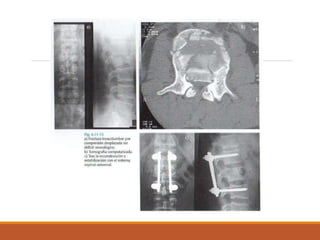

TOMOGRAFIA

POR LO GENERAL SON POCO

INDICADAS

UTILES PARA LA EVALUACION

TRIDIMENSIONAL

CUANDO HAY SOSPECHA DE

LESION NEUROLOGICA

TOMOGRAFIA POR LO GENERALSON POCO INDICADAS UTILES PARA LA EVALUACION TRIDIMENSIONAL CUANDO HAY SOSPECHA DE LESION NEUROLOGICA